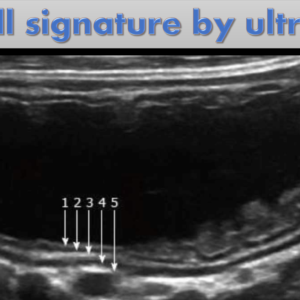

Doppler US (with practical videos) – Basic and Advanced

Radiologist